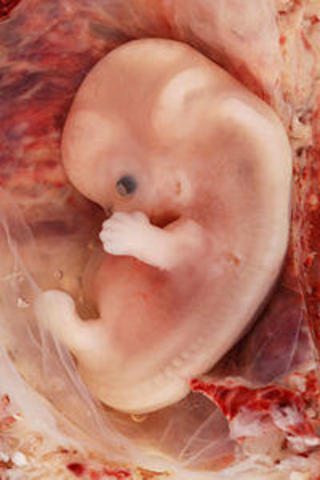

• cuarta semana

cuarta semana

El embrión empieza a desarrollar los vestigios de los futuros órganos y aparatos.El cambio más importante que se produce es el plegamiento del disco embrionario: la notocorda es el diámetro axial de un disco que comienza a cerrarse sobre sí mismo, dando lugar a una estructura tridimensional seudocilíndrica que empieza a adoptar la forma de un organismo vertebrado